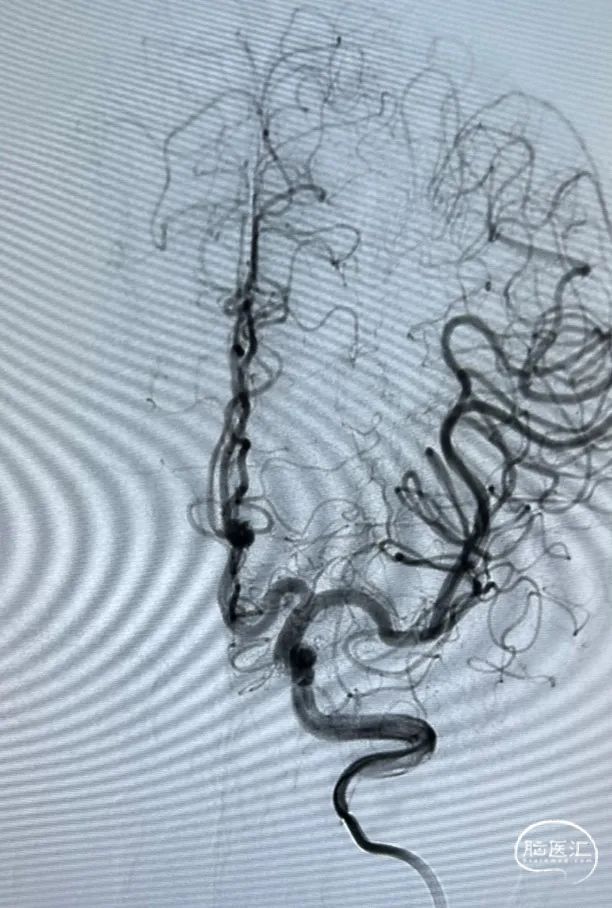

术后造影

治疗后正位减影造影,动脉瘤基本致密栓塞,患者术后无明显不适,术后阿司匹林,波立维双抗。目前一般状况良好。(如下动态影像)

术后造影

术后造影(如下动态影像)。